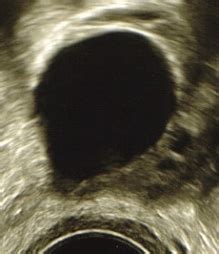

Diagnose von Zysten vs. Follikeln

Die Unterscheidung zwischen einem Follikel und einer Zyste kann mittels Ultraschall erfolgen. Das Vorhandensein von Blut im Follikel, wie manchmal bei einer Größe von 28 mm beobachtet, kann auf verschiedene Faktoren hinweisen und bedarf der ärztlichen Abklärung. Die Verabreichung eines Auslösers wie hCG hilft, die Umwandlung eines reifen Follikels in eine Zyste zu verhindern.

- Ein mit Flüssigkeit gefüllter Hohlraum, der den Teil darstellt, der bei einer Ultraschalluntersuchung sichtbar ist.

Bevor die Ovulation stattfindet, erreicht der dominante Follikel typischerweise einen mittleren Durchmesser von 22 bis 24 mm (mit einer Bandbreite von 18 bis 36 mm).

Ein Follikel von 23 mm Größe wird allgemein als sehr gut entwickelt und reif angesehen. In einem natürlichen Zyklus deutet diese Größe darauf hin, dass der Eisprung in den nächsten 24 bis 48 Stunden erfolgen wird. Bei der Verwendung von Ovulationstests ist es möglich, dass diese noch keinen LH-Anstieg anzeigen, da dieser kurz vor dem Eisprung stattfindet.